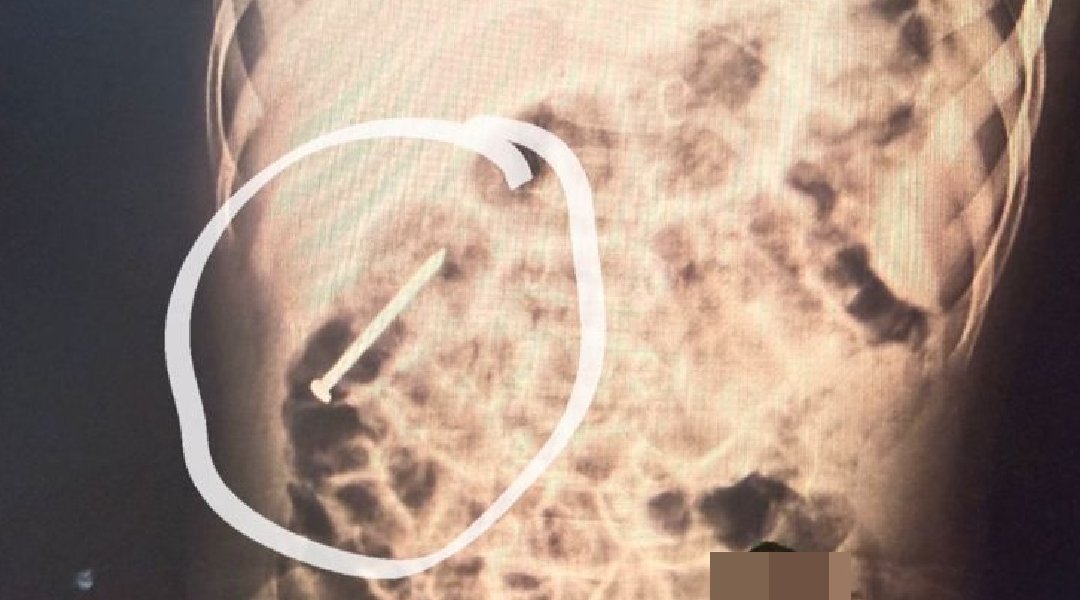

Um menino de dois anos, residente no município de Ipixuna, permanece internado no Hospital do Juruá após ingerir um prego há aproximadamente seis dias. Desde a admissão, a criança está sob observação da equipe médica da unidade.

Segundo os profissionais de saúde, o objeto metálico vem se deslocando pelo sistema digestivo de forma espontânea. Como medida preventiva, o paciente segue hospitalizado para acompanhamento contínuo, enquanto se aguarda que o material seja eliminado naturalmente, sem necessidade de procedimento invasivo.